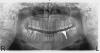

Anna_M Опубликовано 27 сентября, 2013 Поделиться Опубликовано 27 сентября, 2013 Здравствуйте, уважаемые специалисты! Около года назад мне установили имплантат. Все хорошо, полет нормальный Не так давно сделали ОПТГ по другому поводу. Скажите, пожалуйста, все ли хорошо с имплантатом, судя по этому снимку? И, если можно, прокомментируйте, пожалуйста, ситуацию с 47 зубом: меня беспокоит затемнение на снимке - нет ли там разрежения между корней? (Или лучше задать этот вопрос в терапии?) Ссылка на комментарий

Bier Опубликовано 27 сентября, 2013 Поделиться Опубликовано 27 сентября, 2013 С имплантатом все хорошо! А вот 47 зуб требует прицельного снимка. Ссылка на комментарий

Чертков Александр Опубликовано 28 сентября, 2013 Поделиться Опубликовано 28 сентября, 2013 Присоединяюсь. С имплантом все ок. Ждем прицельный 4.7.....п.с. убрал бы 4.8.... Ссылка на комментарий

SergeyAL Опубликовано 25 октября, 2013 Поделиться Опубликовано 25 октября, 2013 чувствительность на холодное характерна для воспаления пародонта, проведите профессиональную гигиену, пакажитесь пародонтологу. с 46,47 и имплантатов все ок))) Ссылка на комментарий